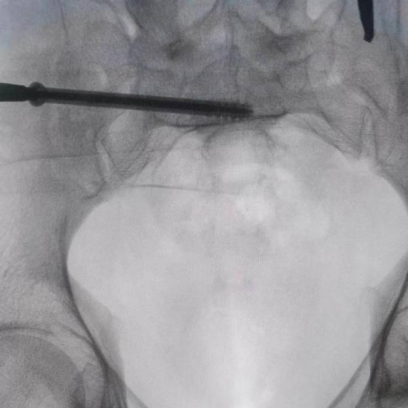

圖為透視下見置入的骶髂螺釘,位置、長度精準,無絲毫偏差